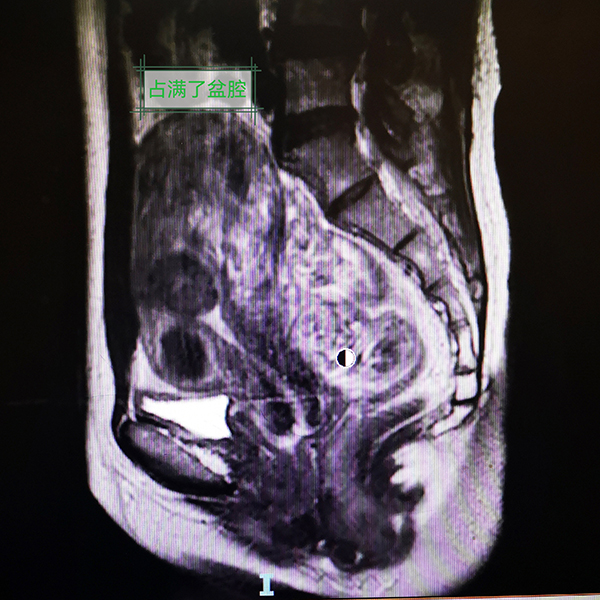

入院后,小杨进一步完善了腹部MRI等相关检查,结果显示她的病情比医生预知的情况更复杂。小杨的阴道只有约1cm长,宫颈阴道全程实性梗阻;盆腔增强磁共振考虑宫颈、阴道发育异常,宫颈闭锁可能,伴宫腔积液/积血;左下腹-盆腔内良性囊性肿块,考虑左侧附件来源病变,出血性囊肿可能;双侧输卵管扩张、积液/积血;考虑盆腔包裹性积液,伴盆腔腹膜渗出改变。经过多学科联合诊疗,医生决定为小杨实施经阴道阴道成型术+宫颈探查+成型术+腹腔镜探查+左侧卵巢囊肿剔除+双侧输卵管伞端造口+肠粘连松解术。

此次手术复杂且难度高,由在生殖道畸形手术方面具有丰富经验的杨岚副主任医师团队实施。术中,医生看到小杨盆腔内广泛粘连、多发包裹性积液(陈旧性血液),双侧卵巢见多个巧克力囊肿,双侧输卵管明显充血肿胀,子宫明显增大。阴道口探入最深1cm,之后阴道结构完全封闭消失形成盲端,未见宫颈结构。在腹腔镜的直视下,B超引导下探针进入宫腔,陈旧的巧克力样积血喷涌而出,残留4年的经血终于顺利流出。同时,腹腔镜下手术逐渐恢复小杨的正常解剖结构。反复下腹痛的“老问题”终于解决了,术后小杨说自己终于睡了个好觉,她母亲脸上也露出了久违的笑容。